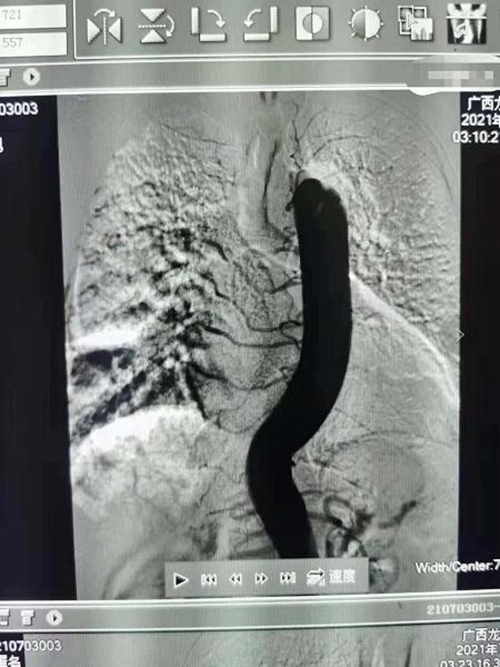

在医护人员的护送下,介入治疗室立即开通绿色通道为患者实行介入手术,经过四个多小时的紧急动脉造影栓塞介入治疗,患者咯血停止,生命转危为安。